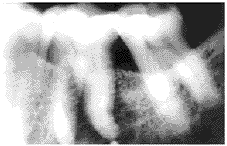

A total of 21 cases of metastatic tumors in the jaws from 1963~1998 were found in the oral tumor registry of Oregon Health Sciences University School of Dentistry. Five of these 21 cases were of breast carcinoma origin. All cases were female. The ages when their metastatic tumor was discovered ranged from 31~63 years. Four cases were in the mandible (three cases in the left and one case in the right) and one case was located in the anterior maxilla (the apex of the right central incisor). Radiologically, all lesions exhibited an ill-defined osteolytic feature(Fig.1a and Fig.2a). Histopathologically, all cases were adenocarcinoma (Fig 1b, Fig 2b). The interval between the primary tumor diagnosed and the appearance of secondary deposit was from 3 months up to 8 years (Table 1). One case exhibited only toothache which led to the discovery of the metastatic lesion. The rest(4 cases in the mandible) manifested swelling, pain, paresthesia, ulceration, secondary infection and bone exposure.

Figure 2a Case 4

Radiograph showing an ill-defined radiolucency associated with a vital right upper central incisor.

The interval between the diagnosis of the primary tumor and that of metastasis in the jaws varied. In our cases, it was from 3 months to 8 years. Bucin et al reported a case where metastasis developed 15 years after the breast carcinoma was first diagnosed[1]. Therefore, five year cure rate is not always significant and long term follow-up is necessary. Symptoms of metastasis when present are pain and swelling of the affected area. Pain may precede radiological evidence of the lesion by as long as 15 months[2] When the mandible is involved, the earliest sign may be anesthesia over the peripheral distribution of the inferior alveolar nerve on the affected side. Loosening of teeth without evidence of periodontitis or pathological fracture has also been stressed as a possible early sign. Pruckmayer et al demonstrated that toothache was the only sign in their four cases of metastatic breast caricinoma in the jaws[4]. In case 4 of our series, a 31 year-old female with a history of spontaneous pain in the area of the right upper central incisor, radiography showed an ill defined radiolucent area adjacent to the apex of the right upper central incisor (Fig 1a). A 1.5 cm slightly raised magenta-colored area on the facial gingiva over the root of the right upper central incisor was seen. The tooth was sensitive to cold. The clinical manifestaion of this case resembled a periapical inflammatory process except the tooth was sensitive to cold[11]. The patient had breast carcinoma which was treated surgically. She had just completed a course of chemotherapy. Her endodontist curetted the apical lesion. Histopathologic examination of the lesion showed an adenocarcinoma (Fig.1b). Chext x-ray revealed both lungs also had metastatic foci. She died 3 months after the metastatic lesions were discovered.

Breast carcinoma in the jaws usually exhibits an ill-defined osteolytic focus radiographically. However, some breast carcinomas may stimulated new bone formation in the metastatic site resulting in radiopaque or mixed radiolucency with opacity[12,13]. These findings may cause difficulty in the differentiated diagnosis radiographically.